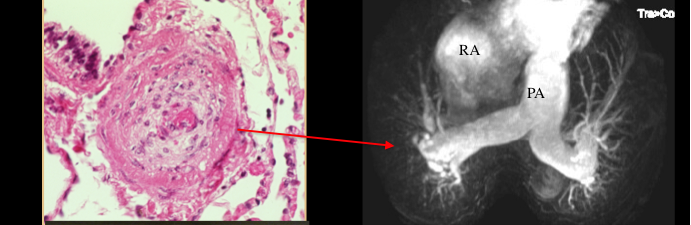

PAH has similarities to lung cancer -too rapid cell growth, impaired apoptosis (although it does not spread (metastasize). PAH also lacks a cure (see below)

Internet image of patient with pulmonary arterial hypertension, a syndrome in which blocked blood vessels in the lung cause shortness of breath and episodes of passing out with exercise. PAH is four times more common in women than men.

Lung blood vessels in PAH are obstructed by proliferating, apoptosis-resistant cells (left) which have a cancer-like phenotype. On the right one can see how vascular obstruction leads to pruning of the lung vasculature (which increases strain on the right ventricle leading to death from heart failure).